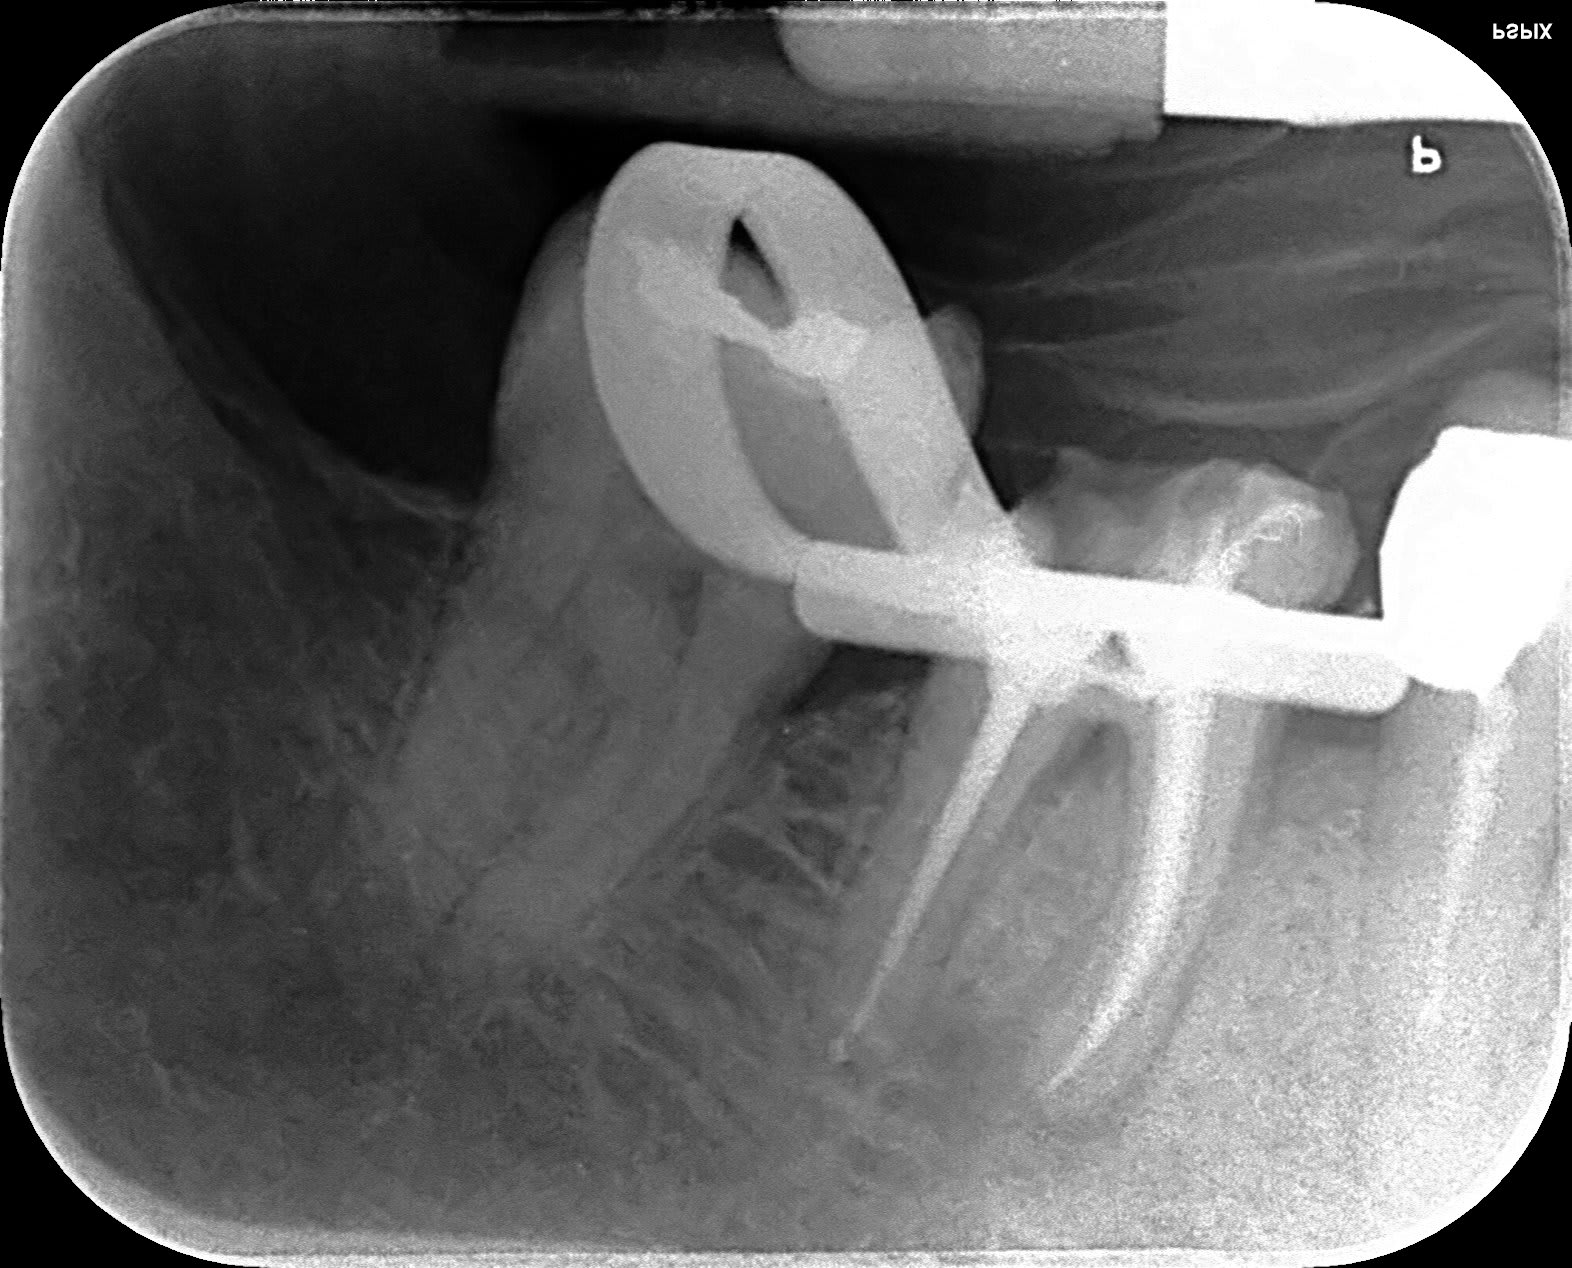

Cas du jour, fracture de la cuspide ML... oui:-) ... je sais... j'ai vu 36. Je vais tenter RTE, CR.

Fracture am unakj0 - Eugenol